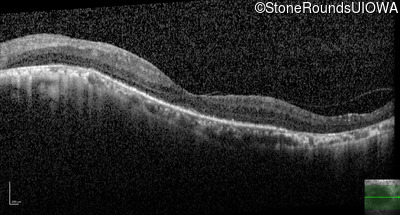

Age at visit: 60 years

This 60 year old man has had poor vision in dim light since about age 10. He lost vision in his right eye at about 16 due to toxoplasmosis. He has a mature cataract in the right eye with no view of the posterior pole. The retina in the right eye is attached by ultrasound.